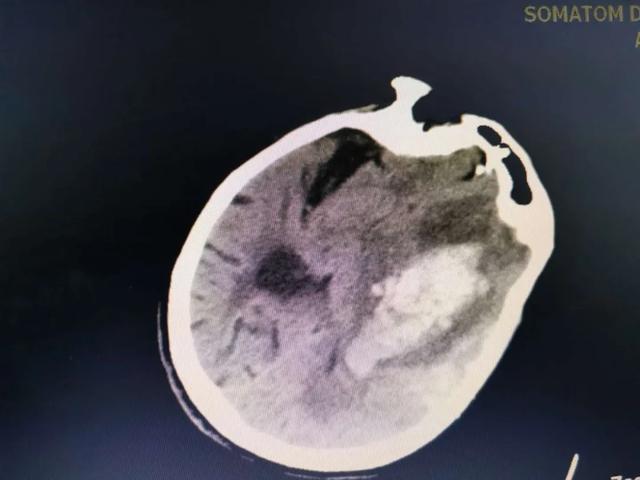

91岁的周婆婆在家中如厕后突然昏迷,肢体活动不利,口吐白沫,家属发现之后立刻拨打郫都区中医医院急救电话,急诊头颅CT提示婆婆发生了脑溢血!收进了ICU!

因为周婆婆已是91岁高龄,加之出血量大,基础疾病多,围术期风险高,预后极差!经脑病科、ICU及患者家属三方综合评估和反复思考后,予以保守治疗。